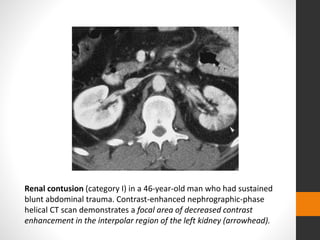

Renal contusion (category I) in a 46-year-old man who had sustained

blunt abdominal trauma. Contrast-enhanced nephrographic-phase

helical CT scan demonstrates a focal area of decreased contrast

enhancement in the interpolar region of the left kidney (arrowhead).